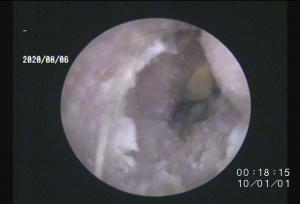

こちらは同一症例の右耳

ちょっと写真がボケてますが・・

カサカサした耳垢が全体的に充満していますね。